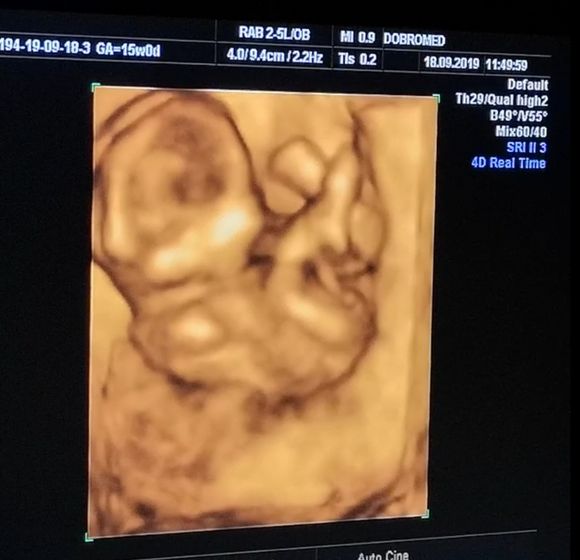

14 недель и 7 дней, нам врач сказала что точно видно мошонку и это мальчик… но я не уверена ? у него пуповина между ног была, короче я запуталась.

На 1 скрининге нам предположили что будет девочка, а тут сюрприз вырос....... Может всё таки пуповина? ?

Видно что мальчик, а в целом какая разница кто, главное что бы зборовый был ребенок

Ага. Видно чётко. Поздравляю с мальчиком ???

Спасибо большое!!! ? Я мечтала о мальчике, хотела первенца мальчишку, и вот сюрприз......